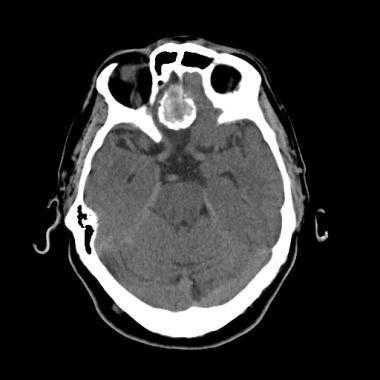

Метастазы головного мозга, фото. На КТ с контрастным усилением у пожилой пациентки (в верхнем ряду слева) с жалобами на головные боли выявлены множественные объемные образования в левом полушарии мозга, интенсивно накапливающие контрастное вещество. Образования имеют характерную форму в виде «кольца». На изображениях в нижнем ряду и вверху справа определяются множественные очаги в головном мозге: отчетливо видны округлые образования с более плотным «ободком» по периферии, располагающиеся в левой теменной доле.